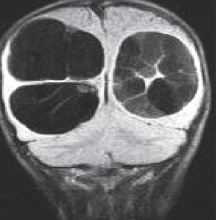

МРТ головного мозга. Т2-взвешенная корональная МРТ. Киста кармана Ратке.

Киста кармана Ратке представляет собой редко встречающееся образование из остатков эмбриональной эктодермы (щель Ратке), расположенное между долями гипофиза. Выявляется в любом возрасте, но чаще в 50-60 лет. Клинические проявления связаны с масс-эффектом. При головного мозга выявляется небольшая (3-5 мм) киста с четким контуром, без отека вокруг, однородная по структуре. Сигнал зависит от содержимого. При серозном содержимом сигнал типично жидкостный, при мукоидном киста светлая на Т1-взвешенных МРТ. В редких случаях киста достигает больших размеров и даже выходит за пределы седла. Стенка кисты иногда усиливается при контрастировании.